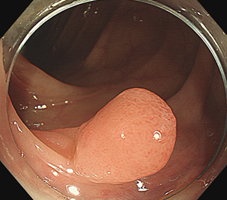

很多人在检查时发现有肠道息肉,一般医生会建议择机切掉,或者当时就顺便切掉,以绝后患。

所以检查中发现比较小的息肉(小于0.5cm的)可以顺便切除,并不会感觉到疼痛。

1、比较大的息肉,在无麻醉切除过程中也会产生牵拉疼,患者会不自觉地挪动身体,这样会影响肠镜医生对肠镜以及手术刀的把控;

3、有的息肉基底比较宽,盲目直接切除会有出血的风险;

5、息肉大于2cm的息肉,要排除有无癌变可能,有无往更深的肌肉层生长。